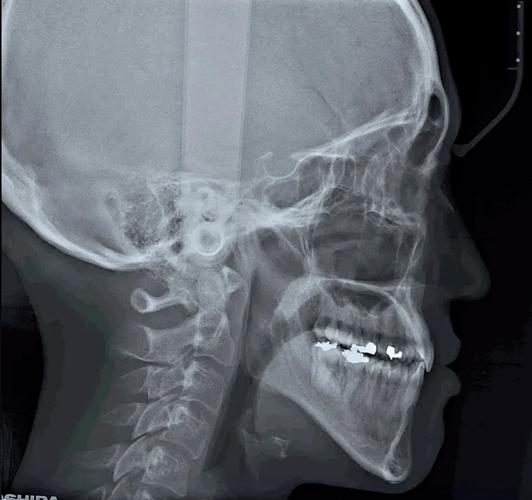

牙齿正畸头颅侧位片是口腔正畸诊疗中核心的影像学检查手段,通过拍摄头颅矢状位的X线影像,全面呈现颅面骨骼、牙齿排列及软组织形态的立体关系,为正畸诊断、方案设计及疗效预测提供客观依据,它与口内曲面断层片、全景片等共同构成正畸影像检查体系,但因能同步评估骨骼、牙齿、软组织的矢状向和垂直向结构,被誉为“正畸诊断的基石”。

- 骨骼关系评估:明确上下颌骨相对于颅骨的位置(如上颌前突/后缩、下颌前突/后缩)、面部垂直生长型(高角面型、低角面型或均角面型),判断骨性错颌的类型与程度。

- 牙齿位置分析:测量牙齿倾斜度(如上前牙唇倾/舌倾)、覆盖覆合关系(深覆盖、深覆合、反颌、开颌)、牙根与牙槽骨的相对位置,评估牙齿拥挤或间隙的原因。

- 软组织形态观察:评估唇部突度、鼻唇角、颏部形态等,预测矫治后软组织侧貌改善效果,尤其是对美学要求高的患者至关重要。

- 生长发育预测:通过骨龄(如颈椎椎体形态、手腕骨化中心)判断患者剩余生长潜力,指导矫治时机选择(如利用青春期生长高峰改善骨性错颌)。